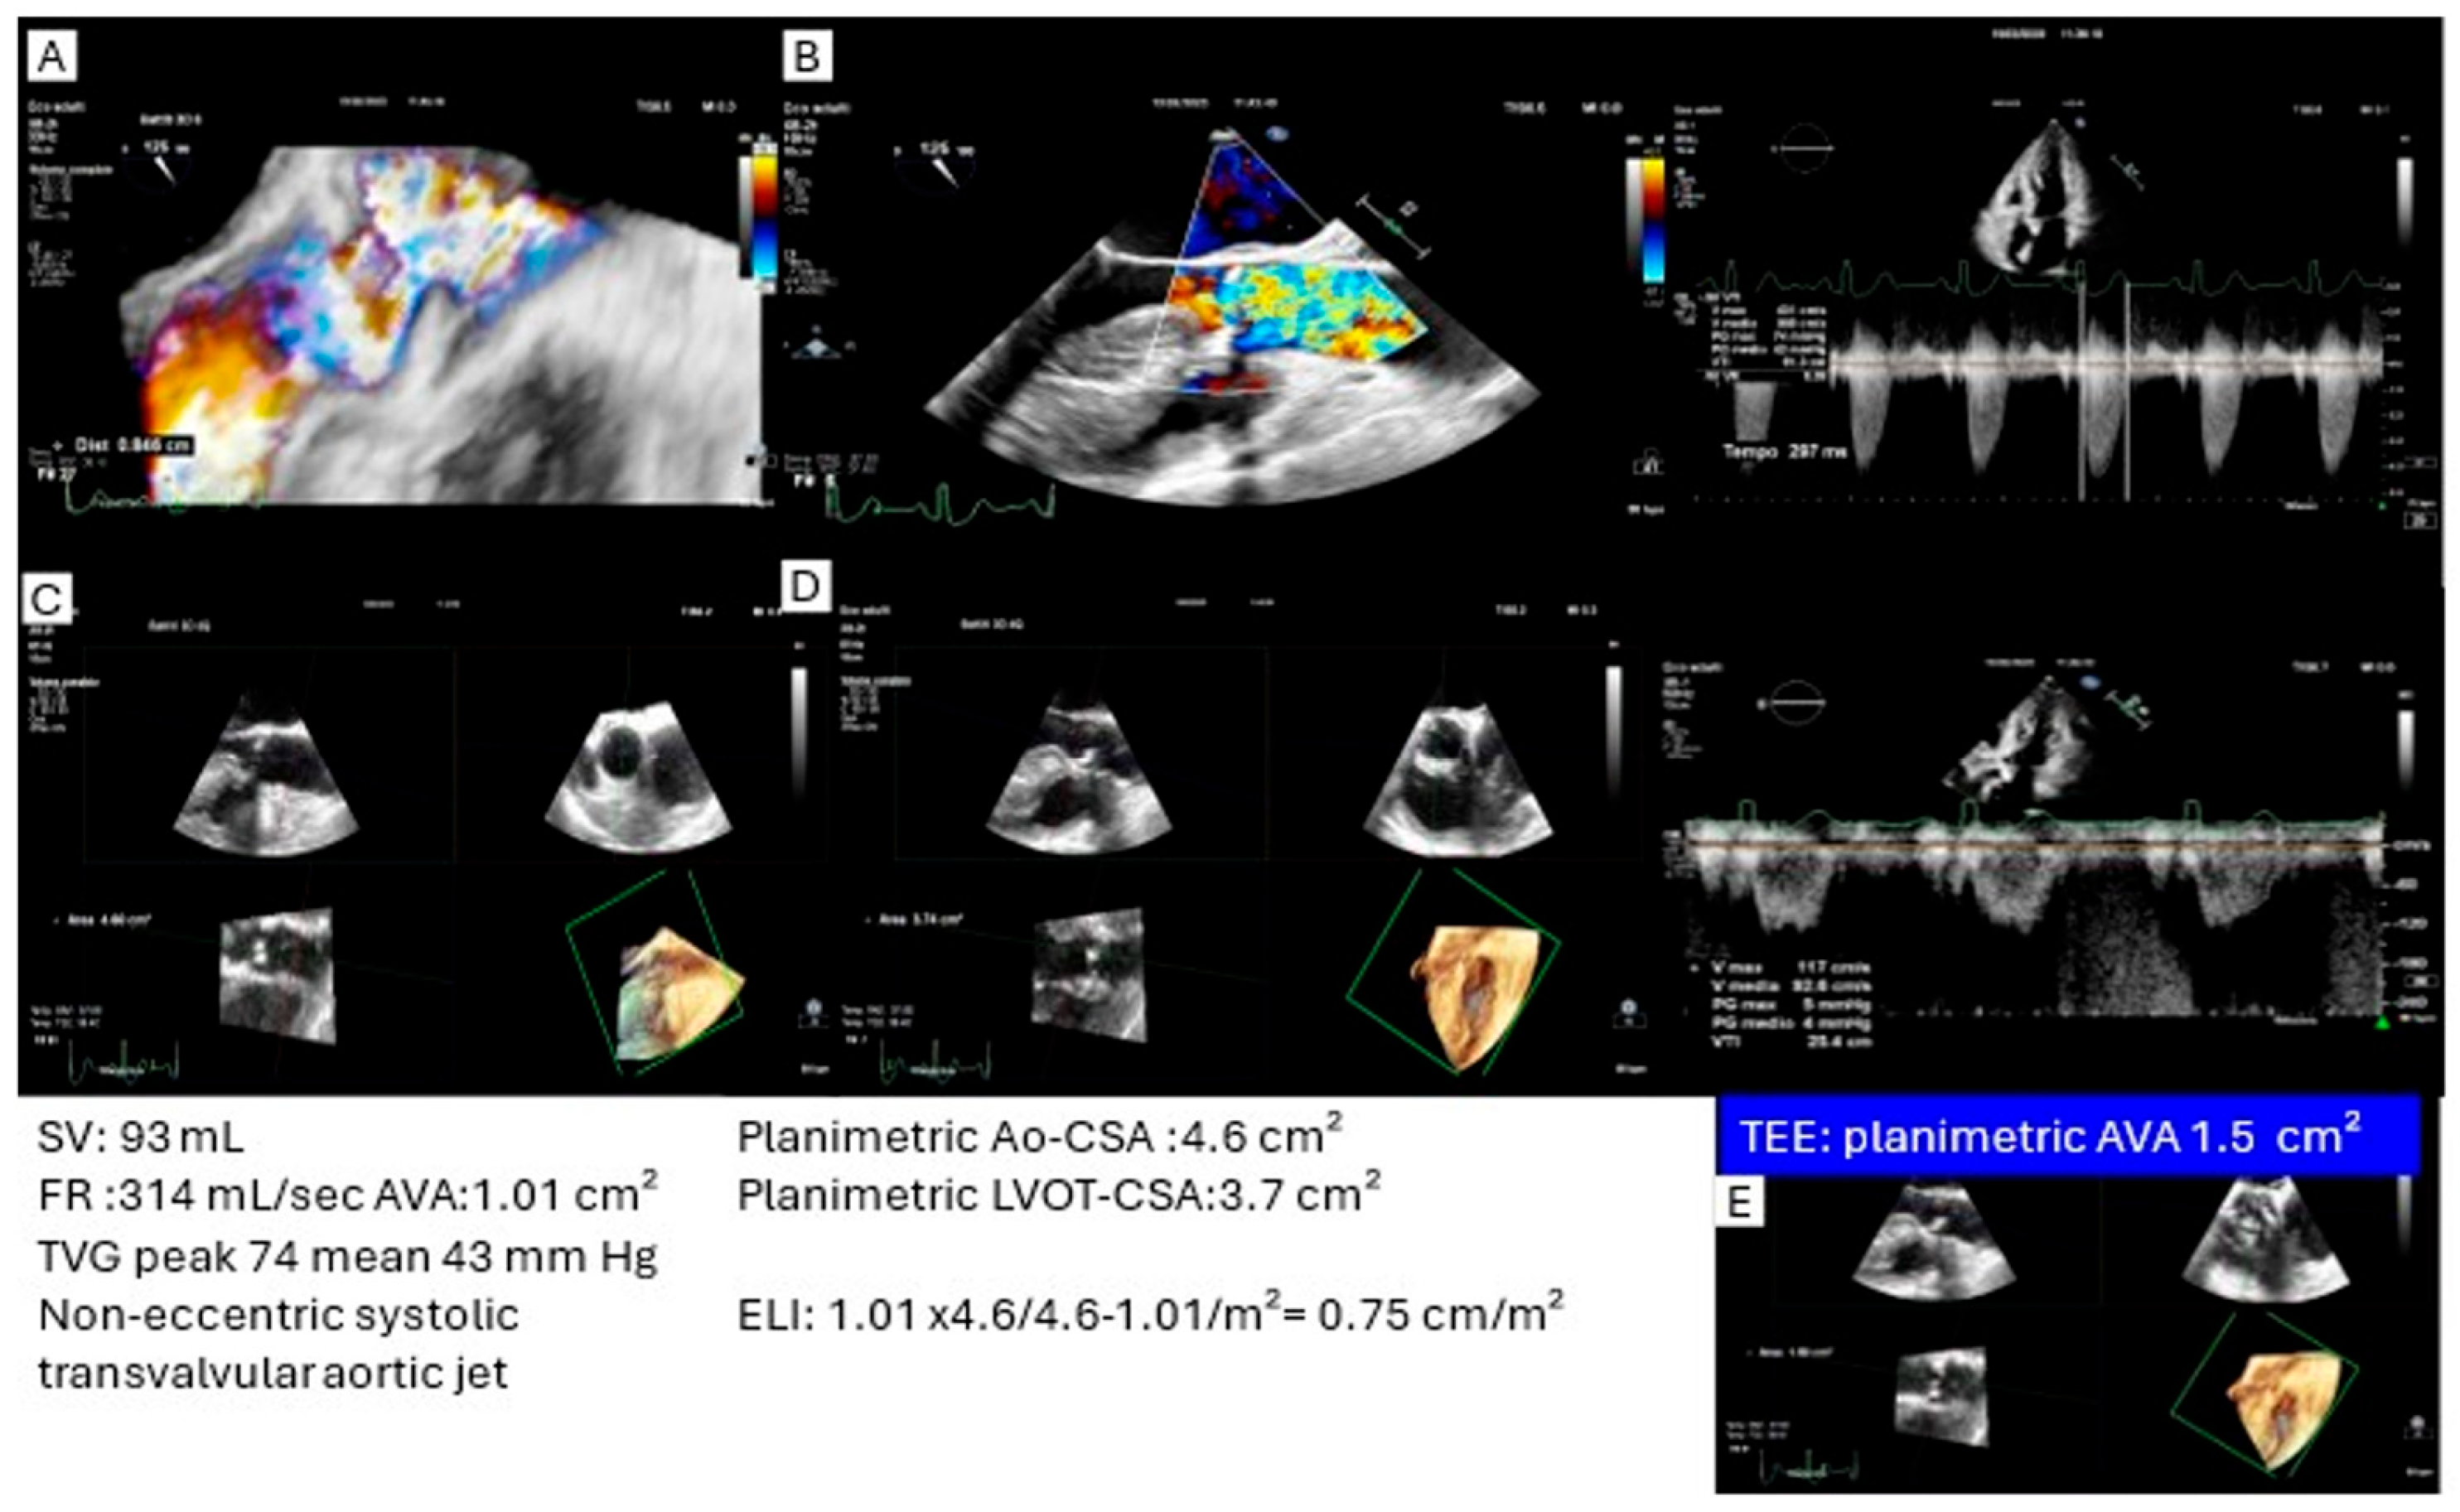

2.1. Transvalvular Aortic Gradient and Pressure Recovery